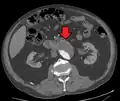

An axial contrast-enhanced CT scan demonstrating an abdominal aortic aneurysm of 4.8 by 3.8 cm